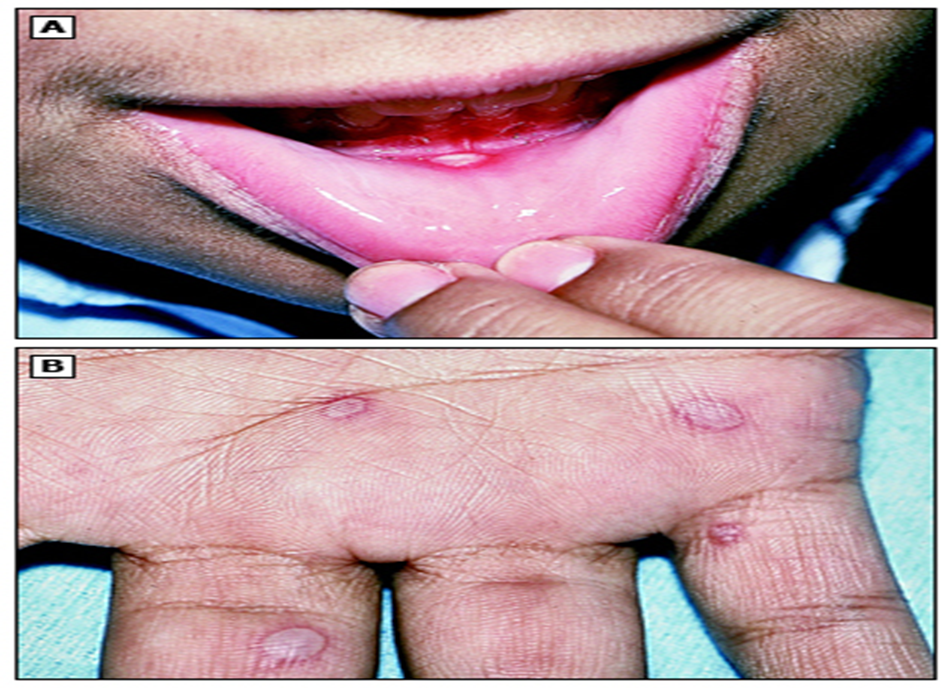

• ხელის, ფეხის და პირის ღრუს დაავადების დამახასიათებელი დაზიანებები (ენტეროვირუსები, განსაკუთრებით EV-A71, CVA16 და CVA6) (სურათი 3A-D).

(სურათი 3A-D).

(ა) პირის ღრუს დაზიანება: ყურადღება მიაქციეთ ერითემის ოვალურ ფორმას და კიდეს.

(ბ) ხელისგულზე შეინიშნება ოვალური, დაუზიანებელი ვეზიკულები.